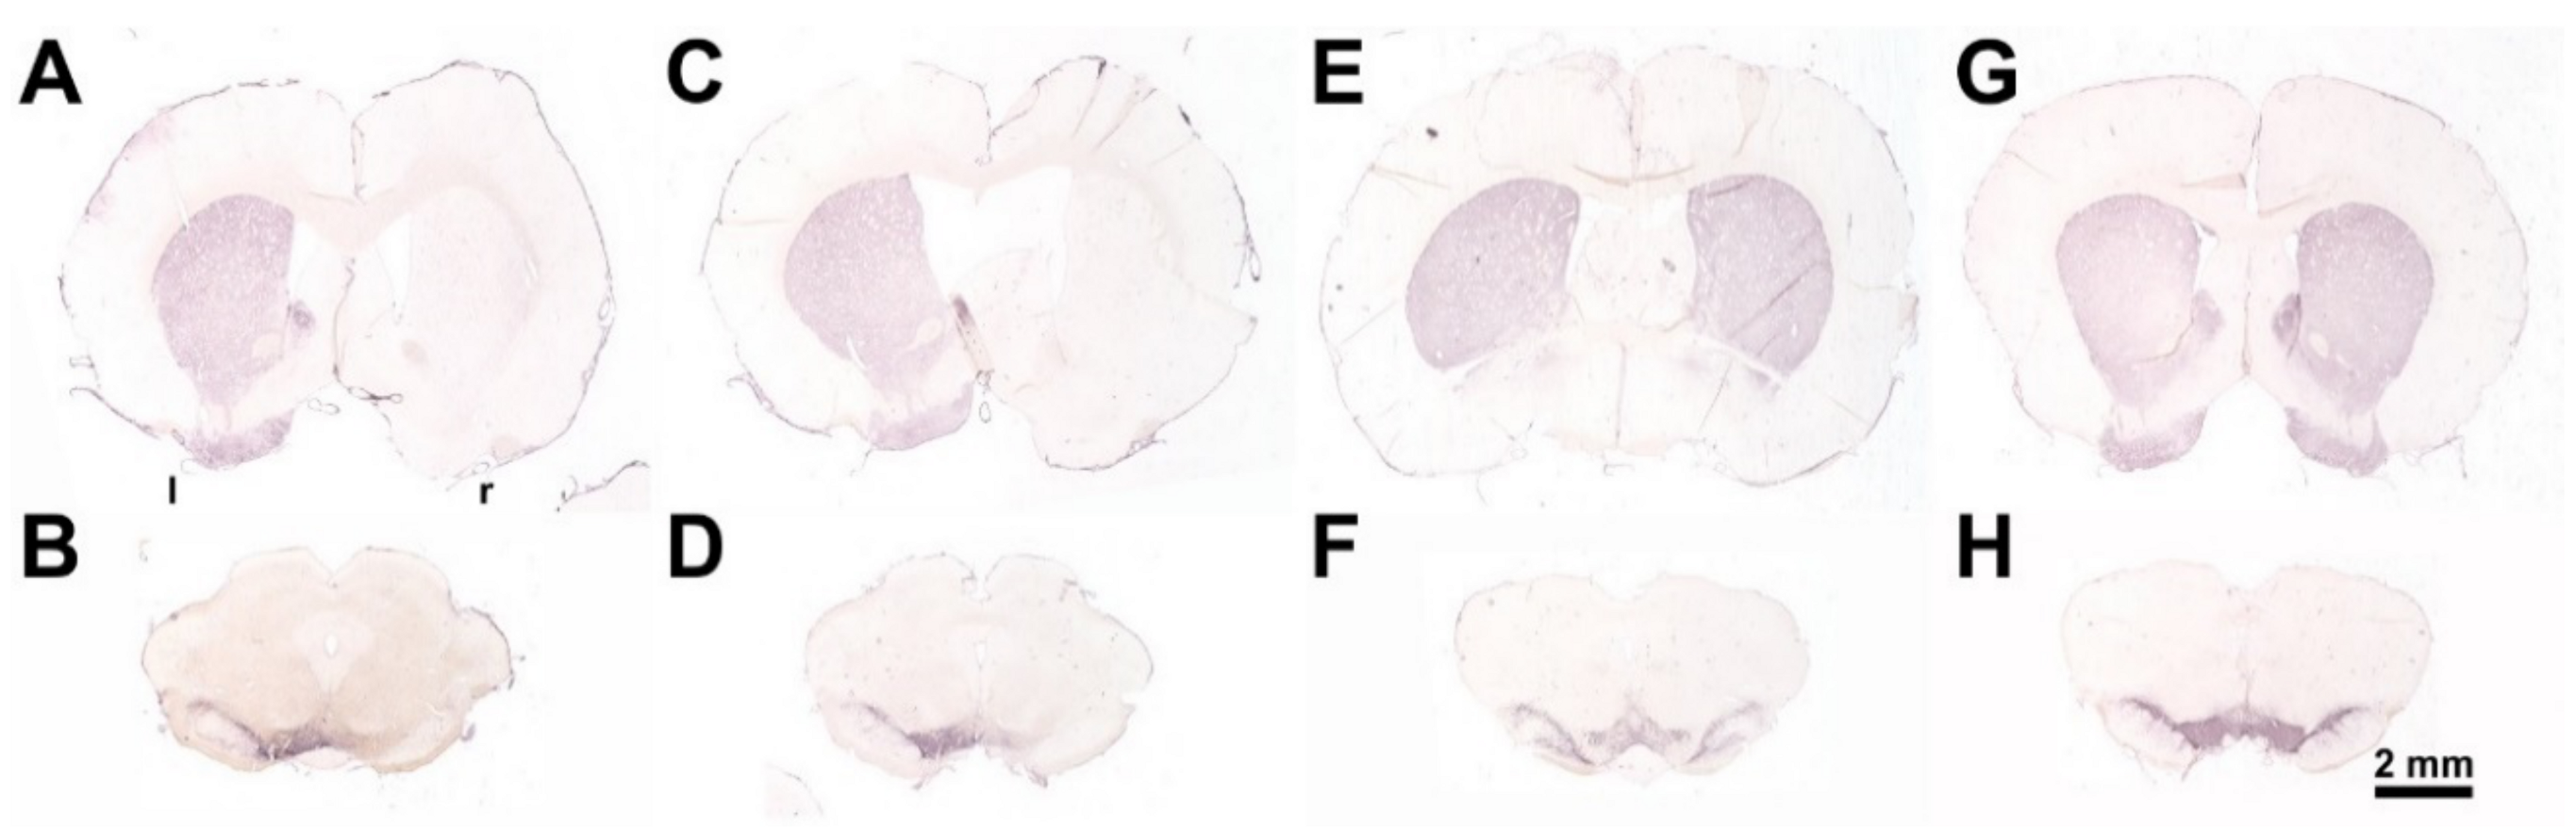

5.2.1. 6-OHDA Lesion Surgery

5.2.2. Injection of BoNT-A into the Striatum